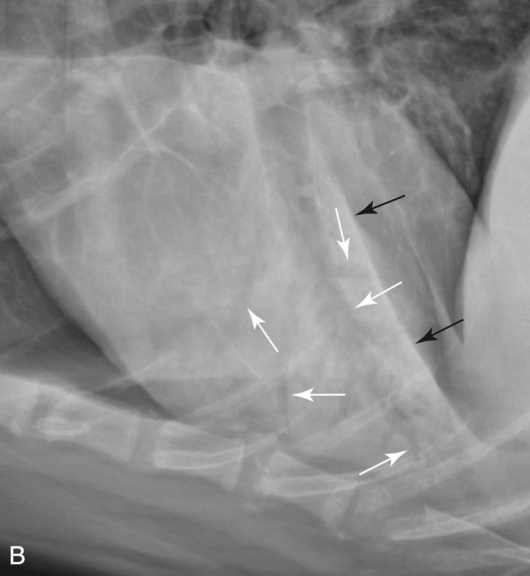

Bronchial signs

Tram line

Doughnuts

๊ธฐ๊ด€์ง€๋ฒฝ ๋‘๊บผ์›Œ์งˆ ๋•Œ ๋ณด์ด๋Š” sign

ํ ๋ง๋‹จ์œผ๋กœ ๊ฐˆ์ˆ˜๋ก ๊นจ๋—ํ•œ ๊ฒŒ ์ •์ƒ

๋ง๋‹จ์—๋„ tram line ๋ณด์ด๋ฉด ๋น„์ •์ƒ

VS.

(์™ผ์ชฝ์ด ์ •์ƒ, ๋ง๋‹จ์œผ๋กœ ๊ฐˆ์ˆ˜๋ก ๊นจ๋—. ๋ง๋‹จ์—๋„ tram line ๋ณด์ด๋Š” ์˜ค๋ฅธ์ชฝ์€ ๋น„์ •์ƒ.)

ํฐ์ƒ‰: doughnuts, ๊ฒ€์€์ƒ‰: trams)